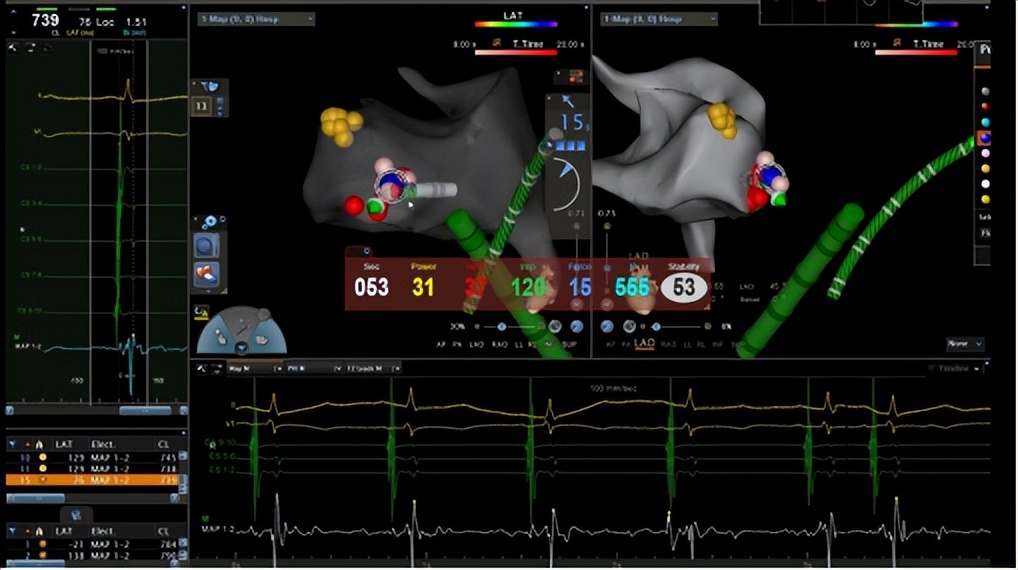

手术的关键,是找到心脏里的“异常激动点”。郑全主任团队通过股动脉送入射频导管,在三维导航仪指引下,在心脏主动脉瓣二尖瓣连接处(AMC区域)精准定位。

△术中三维导航,确定异常病灶,治疗快速性心律失常

“就像用精准导弹打掉靶点!”随着射频电流释放,异常病灶被彻底消融。整个手术仅用1小时,创口只有米粒大小。术后第三天,夏先生就康复出院,心悸症状完全消失。